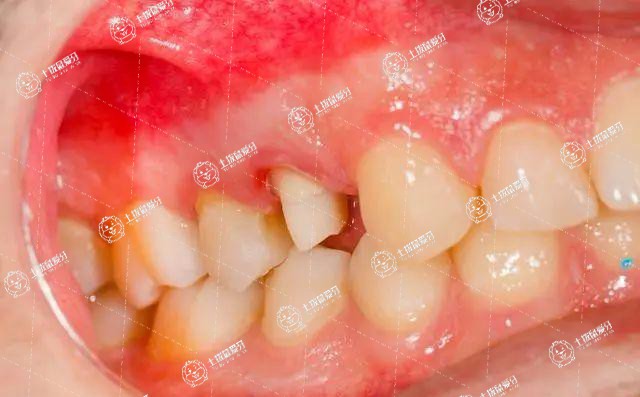

拔完智齒以后,有的會(huì)覺得前面的牙有酸痛,是因?yàn)榘瓮曛驱X以后,相鄰牙的后面,醫(yī)學(xué)上稱為遠(yuǎn)中面的牙頸部會(huì)暴露。有離得比較近的,可能有部分牙根也暴露。

牙冠的表面有牙釉質(zhì)覆蓋,牙根的表面有牙骨質(zhì)覆蓋,只有在牙頸部,會(huì)有一些薄弱的區(qū)域沒有牙釉質(zhì)或者牙骨質(zhì),露出了牙本質(zhì)。

矯正牙齒前拔了智齒牙齒會(huì)變松嗎

牙本質(zhì)里邊有神經(jīng)末梢,容易受到外界刺激而產(chǎn)生不適的感覺。所以,如果一旦牙頸部的牙本質(zhì)暴露,會(huì)出現(xiàn)酸疼,這樣的癥狀可能要持續(xù)一段時(shí)間,隨著牙槽窩的愈合,慢慢的骨化就會(huì)蓋上牙頸部,這時(shí)酸痛的感覺就消失了。

如果智齒是近中阻生,與前面牙齒相鄰,前面牙齒遠(yuǎn)中沒有非常多的骨,那么拔完智齒之后,前面牙齒遠(yuǎn)中就會(huì)有牙頸部甚至牙根暴露,那么就會(huì)出現(xiàn)酸的現(xiàn)象,我們認(rèn)為這是正常現(xiàn)象,等到智齒的拔牙窩愈合之后,前面的牙齒的牙根暴露就不會(huì)那么明顯,所以酸痛也會(huì)緩解。